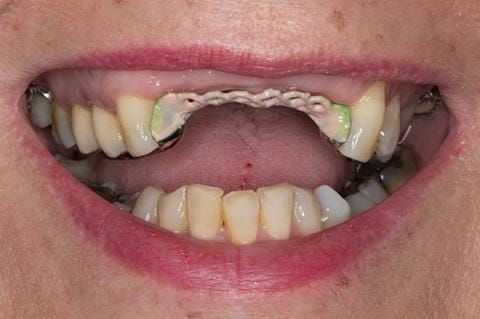

Provision of a maxillary cobalt chromium based partial denture/protective occlusal splint in a heavily restored dentition

- High smile line showing gum above gingival zeniths of upper front teeth when smiling. Aesthetic failure of the upper four incisors with inflammation of the gingivae and mis-match of the gingival zenith levels.

Following consultation and second discussion appointment the patient chose to have option 3 namely, a maxillary cobalt chromium based partial denture/protective occlusal splint. The clinical situation and treatment process is shown in detail below with photographs. The patient was successfully rehabilitated with this and her quality of life considerably improved. The clinical work was provided by Finlay and the technical work by Rowan.